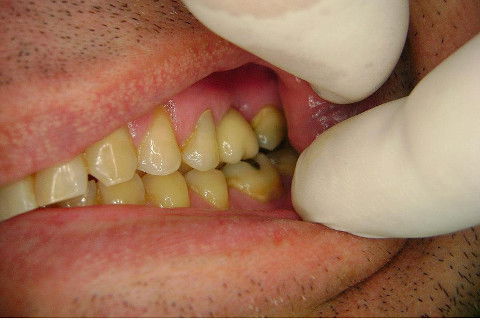

Instalação de um implante em região do 26. Utilizamos um implante cone morse Alvim Neodent 4.3 X 11,5. Foi uma cirurgia muito rápída e minimamente traumática, sem retalho e sutura.